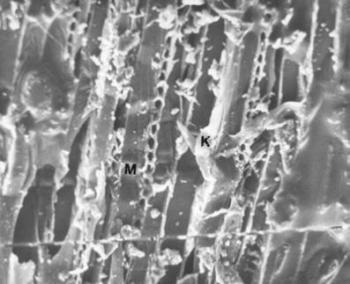

88. ábra. Fogkőbe beágyazódott hús(izom-) darabka. M= izomsejt, K= endomysialis kötőszövet. SEM 1400× nagyítás

A fogkövek vizsgálatát ritkán végzik, mindössze néhány tudósítás olvasható, noha a szájüreg flórájára, a táplálék minőségére, olykor a konyhatechnikára is felvilágosítást szolgáltathat. Dr. Török Katalin fogorvossal közösen végeztük el 20 váci múmia (30-68 év közöttiek) fogköveinek mikroszkópos elemzését. Valamennyiben kimutathatók Gram pozitív és negatív pálcák, Gram pozitív coccusok, de sohasem találtunk Gram negatív coccust. Három alkalommal gombatelepek illetve gombaspórák látszottak (85. ábra, 86. ábra, 87. ábra). Ez arra utal, hogy az idők folyamán jelentősen megváltozott az emberi szájflóra, ugyanis a neandervölgyi ember fogkövében csak pálca alakú baktériumokat (Pap és mtsai 1995 és 1996), egy ősindián temető anyagában viszont kizárólag coccusokat találtak (Magennis és Cummings 1996), a recens fogkövek mikroba összetétele fajgazdagabb (Silvestrini és mtsai 1992). A 18–19. században jelenhettek meg a gombák a szájüregben (10. táblázat). Roberts és Woodward (1996) két angliai temető leletein a fogkövek ételmaradványait tanulmányozva azt állítják, hogy nem lehetett lényeges különbség a lepratelep lakóinak és a telepen kívül élőknek a táplálkozása között. Magennis és mtsa (1996) mexikói ősindián populáció fogköveiben kukorica-keményítő szemcséket, perjefű-félék maradványait, fitolithokat azonosítottak. Valamennyi esetünkben növényi rostok, kristályok és fitolithok (90. ábra), kétharmadukban búza-, kukorica-, burgonyakeményítő szemcsék (89. ábra) fordultak elő, de rizskeményítővel sohasem találkoztunk. A 18–19. században mind a kukorica, mind a burgonya fontos néptáplálék lehetett. A fogkőbe zárt kollagénrostrészletek hőkárosodást mutattak, jelezvén, hogy nem nyers (kolbász, füstölt sonka, szalonna), hanem hőkezelt (sütött, vagy főzött) ételből származnak. Izomrostokat két alkalommal találtunk, számos képletet nem tudtunk azonosítani (85. ábra, 86. ábra, 87. ábra, 88. ábra, 89. ábra, 90. ábra).